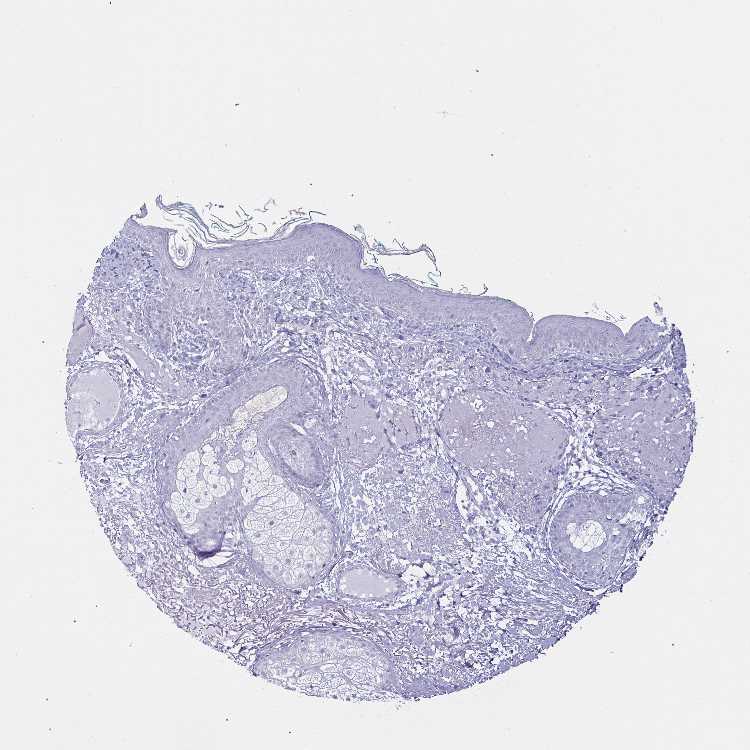

SKIN 1 - Antibody stainingi

Antibody staining in the annotated cell types in the current human tissue is reported as not detected, low, medium, or high, based on conventional immunohistochemistry profiling in selected tissues. This score is based on the combination of the staining intensity and fraction of stained cells.

Each image is clickable and will lead to virtual microscopy that enables deeper exploration of all samples and also displays staining intensity scores, fraction scores and subcellular localization as well as patient and tissue information for each sample.

Antibody HPA019462

Langerhans Not detected

Fibroblasts Not detected

Keratinocytes Not detected

Melanocytes Not detected

SKIN 2 - Antibody stainingi

Epidermal cells Not detected